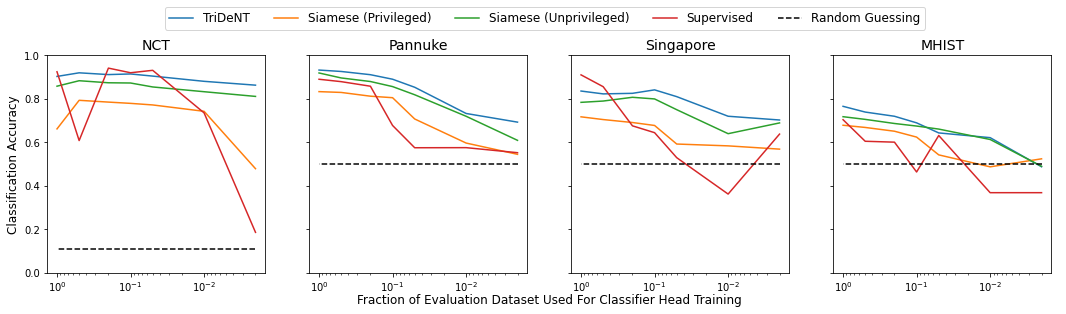

2.1.1 TriDeNT ♆ Pretrained Models Outperform Supervised Models on Small Datasets

In Fig. 2(d) we demonstrate that TriDeNT ♆ consistently retains a higher level of performance as less classifier training data is used. Notably, there are dataset sizes where supervised and privileged Siamese models collapse to a trivial solution, while TriDeNT ♆ continues to perform well. The ability to learn well from tiny, few-shot classification datasets is evidence of the utility of models trained with TriDeNT ♆ for a variety of downstream applications, as in many biomedical settings there are very few samples available for a given topic of interest. TriDeNT ♆ can allow researchers and clinicians to make use of these few-shot datasets to enable the study of previously unworkable datasets.

3.2 TriDeNT ♆ Does Not Need Large Datasets

Self-supervised methods typically require very large datasets [35], however our results, especially those for PanNuke (Section 2.3) and ALS-ST (Section 2.4), demonstrate that TriDeNT ♆ offers improvements over comparable baselines for comparatively small pretraining datasets. We also studied the effect of evaluation dataset size in Section 2.1.1, showing that TriDeNT ♆ continues to achieve strong performance even when the classifier head is trained on a tiny dataset. This perforance can only be expected to improve further if pretrained models are used, either from a general source such as ImageNet [36] or from more specific pretraining tasks. We expect that this would be particularly useful in cases where the privileged paired model is pretrained, as teacher-student distillation would likely lead to greater performance in the student (primary) model.